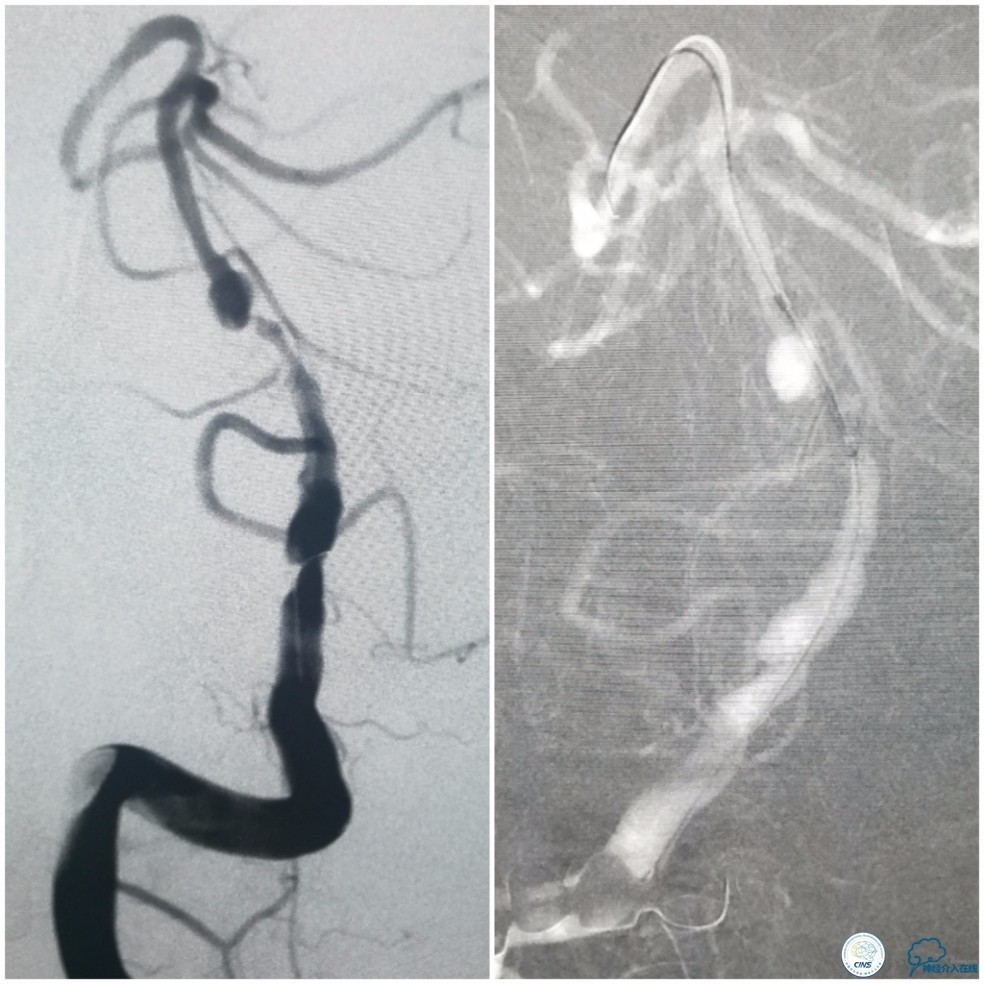

撤出Echelon-10微导管及5F导引导管。沿6F导引导管送入Select Plus微导管至基底动脉远端。经微导管送入Enterprise 4.5mm×28mm至右椎动脉V4段,两个支架重叠约2-3mm,完全覆盖右椎动脉V4段夹层(图13)。

图13

动脉粥样硬化狭窄合并动脉瘤的处理,因治疗狭窄和栓塞动脉瘤的两套系统常需要并列使用,事先要考虑所用导引导管是否能完全容纳两套系统,如本例8F导引导管到位困难,故只能改用两套系统完成治疗(图14)。

图14